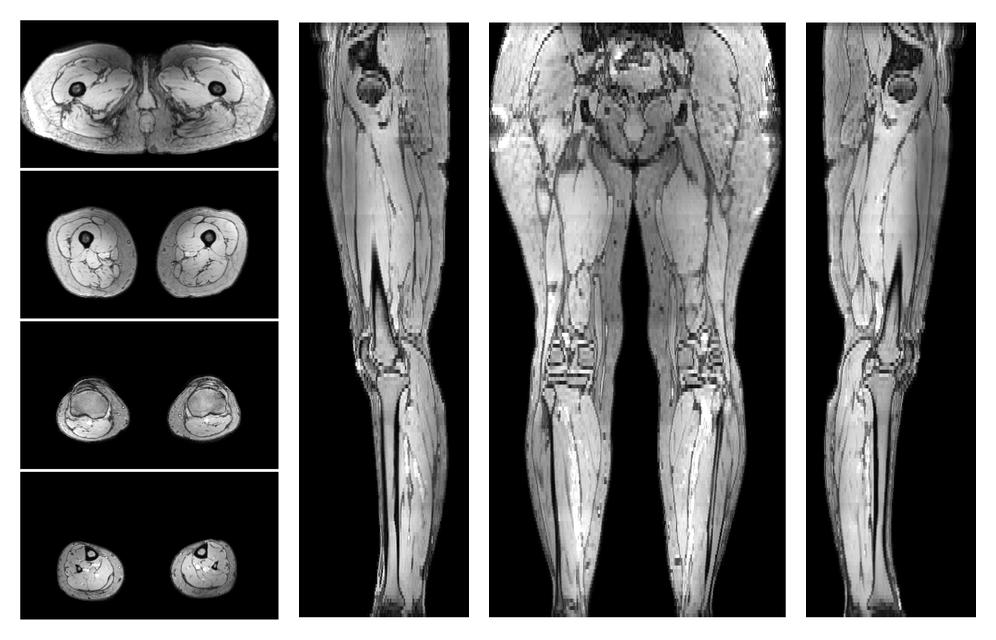

• Out phase image

The out-phase image of the dixon reconstruction for water fat quantification.